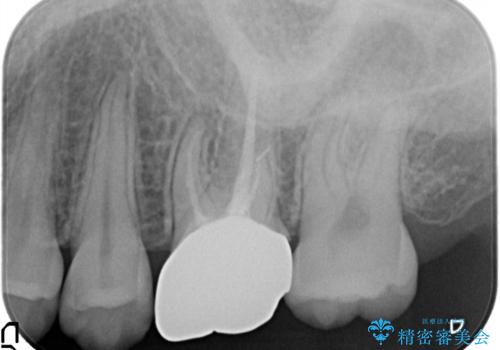

被せ物を除去し、根管治療を進めた後に新しい被せ物を装着していきます。

- 左上6:仮歯+ジルコニアクラウン/11,000円+121,000円 , 再根管治療(リトリートメント)+土台(ファイバーコア)/143,000円+22,000円費用は治療当時の料金となります

本来は歯茎をしっかりと下げる外科処置が適応となるケースでしたが、ご希望がなかったため最小限の侵襲に抑えて治療を行いました。

根の中を洗浄し、結果的に適合の良い被せ物をセットすることができました。